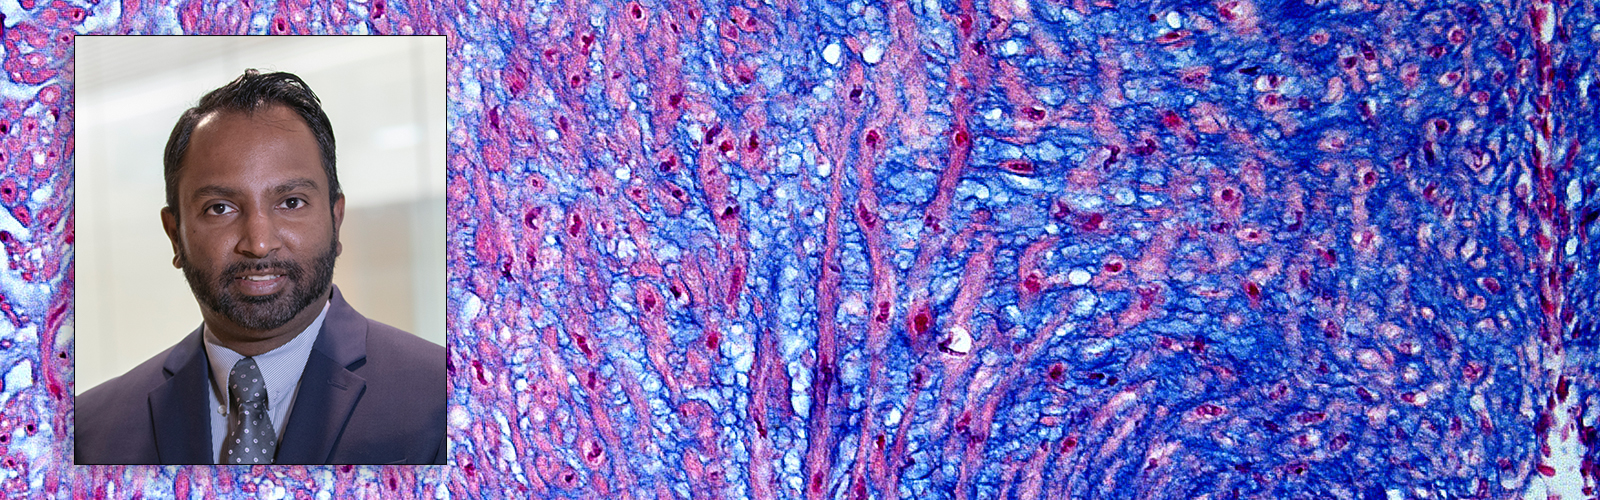

Nandadasa Primary Cilia and Extracellular Matrix Lab

The research in the Nandadasa laboratory is focused on understanding the function of extracellular matrix proteases belonging to the ADAMTS family of metalloproteinases in embryonic development and in disease. Specifically, we investigate a group of developmental birth defects known as ciliopathies that arise by the dysgenesis of the primary cilium, a crucial antenna-like cellular organelle, present in nearly all cells. ADAMTS proteases (A disintegrin and metalloproteinase with thrombospondin type 1 motifs), are secreted molecules mainly known to act on the extracellular matrix. In paradigm-shifting discoveries we have shown that ADAMTS9 and ADAMTS20 are endocytosed and recycled to the ciliary vesicle in Rab11+ vesicles and that they play crucial proteolytic functions leading to primary cilia formation. ADAMTS9 mutations cause nephronophthisis (NPHP) and Joubert syndrome (JBTS), two devastating ciliopathies which are diagnosed in young children and infants.  Adamts9 and Adamts20 mutant mice available to us manifest severe embryonic defects resembling human ciliopathies and provide valuable disease models. The goals of our research are to: